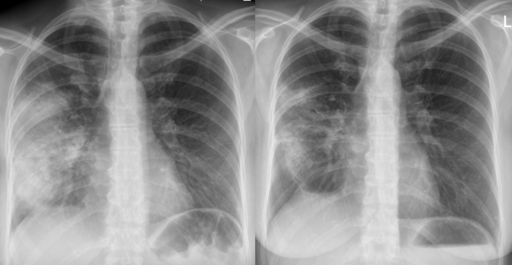

Radiografía de tórax

El diagnóstico definitivo de la NAC requiere evidencia de consolidación en una radiografía de tórax (RXT). Por lo tanto, se recomienda realizar una RXT a todos los pacientes ingresados en el hospital lo antes posible, idealmente en las primeras 4 horas tras el ingreso.

Imagen radiográfica de neumonía antes (izquierda) y después (derecha) del tratamiento con antibióticos.

Neumonía aguda

Hellerhoff, CC BY-SA 3.0, a través de Wikimedia Commons